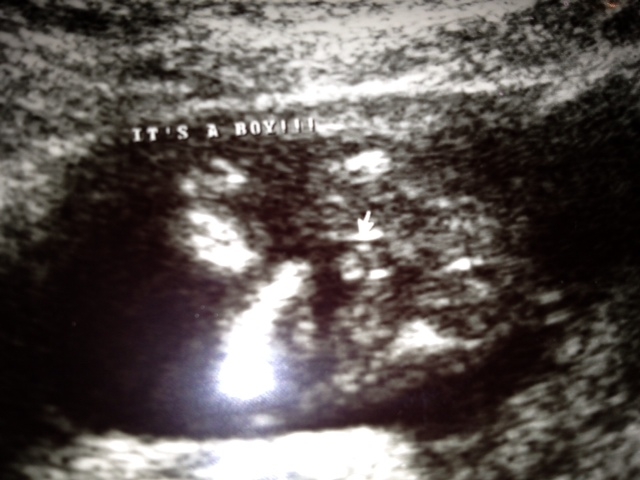

15w2d gender shot

Hello everyone! I am new to the gender dreaming site but I was hoping that you all could weight in on my 15w2d ultrasound shot. The tech said that she thought it could be a boy based upon the area that I circled in blue, but right behind the blue circle there are three white lines (circled in pink). Adminttedly I didn't noticed the white lines until my neighbor (a nurse) pulled the image up on her computer and blew it up really large.

I drew in the legs in with green lines and I also circled the hand in orange. If these are boy parts, aren't they rather large for 15w2d?!? I ask because the baby had the cord inbetween the legs for the majority of the scan and I'm wondering if it is indeed boy parts or a shot of the cord that looks like boy parts.

At this gestation with my older son, his parts were much smaller - but I do know that babies can be swollen. Would you trust this photo as a boy???

And without markups...

Attachment 7535